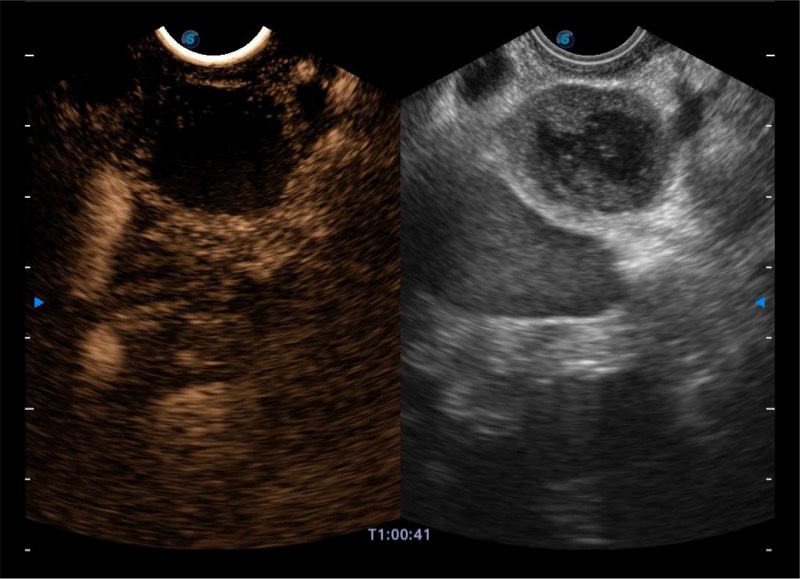

搭载百万级CMOS成像技术

及自主研发凸阵换能器,

可呈现优质的内镜和超声画面

基于二十年的超声技术积累,诸侯快讯官网提供了最新一代的独立超声主机,在提供高质量图像的同时满足多学科使用。具备常见多普勒技术并提供弹性成像、声学造影等高端影像技术。新一代传感器具有更强的抗干扰能力并减少图像伪影。

4-12MHZ宽频输出